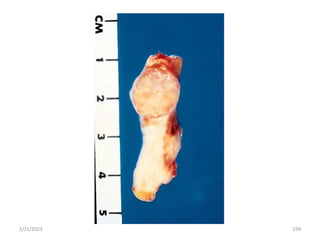

…

Polyp

 A mass that projects above a mucosal surface to

form a macroscopically visible structure.

 e.g. colonic polyp, nasal polyp